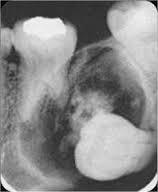

Buccal Bifurcation Cyst

Inflammatory cyst with uncertain pathogenesis

Develops on BUCCAL aspect of the mandibular 1st permanent molar (2nd molar) – PARTIALLY ERUPTED

Pushes the crown buccally and the roots lingually (develops below CEJ)

Occurs in avg age of 10

Symptoms: Tenderness, swelling, or fout tasting discharge